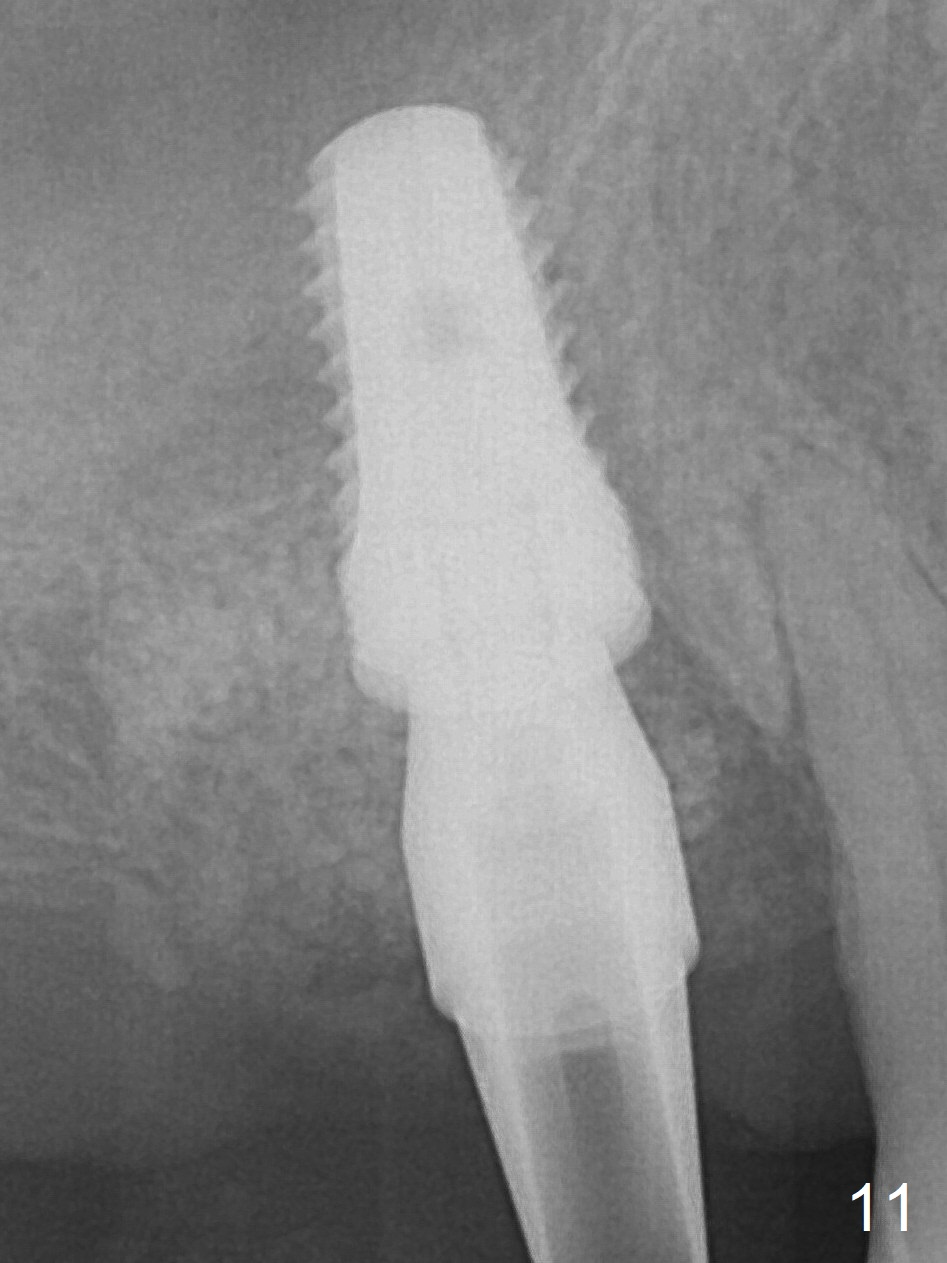

After extraction of the tooth #3 (Fig.1,2), the palatal socket (P) is as wide as the buccal one (B; Fig.3,4 (socket impression)), as compared to the roots), suggesting bone loss is more severe palatally than buccally. There is a circular area in the buccal slope of the palatal socket, in which the bone looks thin (purplish: presumably the sinus membrane underneath, Fig.5,7 (blue circle)). It appears that the palatal slope of the buccal socket (Fig.6, 7 red dashed line) is the most appropriate site for osteotomy (Fig.8). Prior to inserting 5.3 mm tap drill (Fig.9), the mesiopalatal region of the osteotomy (corresponding to the blue circle in Fig.7) perforates without sinus membrane tear. A small piece of Osteogen plug is placed in the perforation before inserting a 5.3x10 mm SM implant (Fig.10,11). Following placement of another piece of Osteogen plug in the palatal socket and of a 4.8x7(6) mm abutment, mineralized cortical and cancellous bone is placed (*). Collagen plug and an immediate provisional are used to close the socket opening. CT taken 11 months post cementation shows that the implant is placed within bony boundary, although buccally (Fig.12 B). Bone graft seems to heal in the sinus (Fig.13 (sagittal section),14 (coronal section) white * (Osteogen plug) and in the socket (brown * (allograft and Osteogen)).